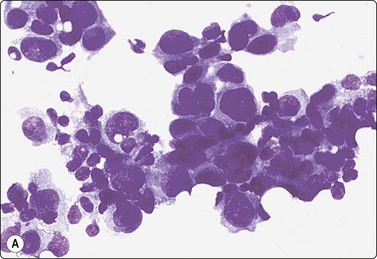

image image

Fig. 7.1 Radiation-induced atypia

(A) The epithelial cells in this irregular cluster show considerable nuclear enlargement, pleomorphism and hyperchromasia, but also some degenerative changes such as loss of nuclear structure (MGG, HP); (B) Corresponding tissue section (H&E, IP).